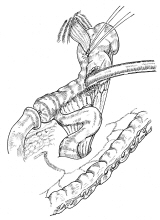

器械吻合器テクニックあれこれ

あのころ、実用化されたばかりの自動吻合器の使用上の「コツ」シリーズ。